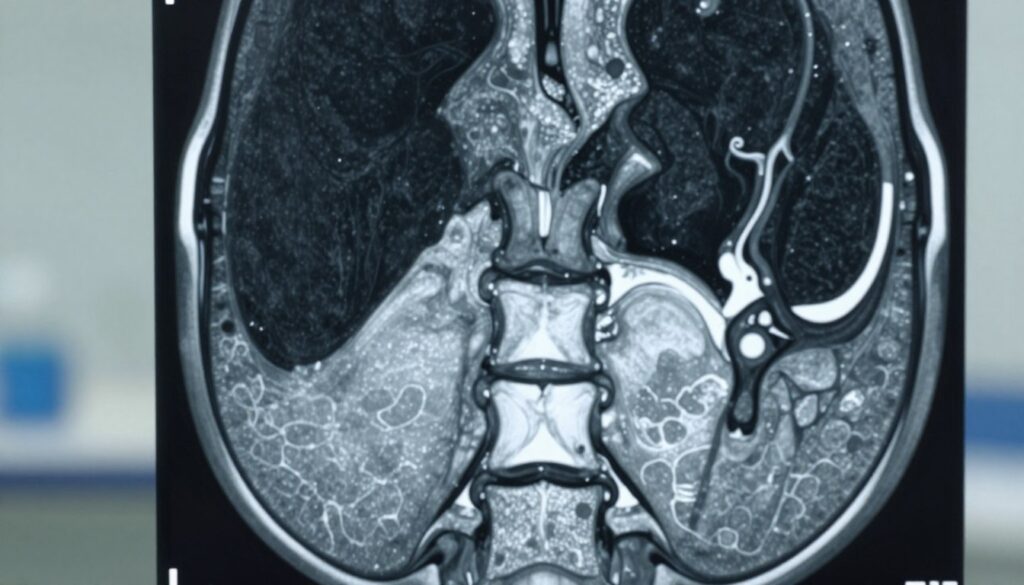

MRI pozwala ocenić nie tylko kości, lecz także krążki, więzadła, mięśnie, kanał kręgowy i rdzeń. W opisie lekarz szuka ustawienia kręgów, stanu krążków oraz ewentualnego ucisku struktur nerwowych.

Analiza obrazów koncentruje się na trzonach kręgów, łukach i stawach międzykręgowych. Radiolog sprawdza też krążki międzykręgowe pod kątem odwodnienia, uwypukleń i przepuklin.

W praktyce badania oceniają, czy kanał kręgowy jest zwężony oraz czy dochodzi do ucisku rdzenia kręgowego. To kluczowe przy podejrzeniu dyskopatii lub stanu zapalnego.

- Rezonans umożliwia wykrycie guzów, krwiaków i zmian pourazowych niewidocznych w RTG.

- Opis badania zawiera lokalizację, rozmiar i cechy zmian, co kieruje dalszym leczeniem.